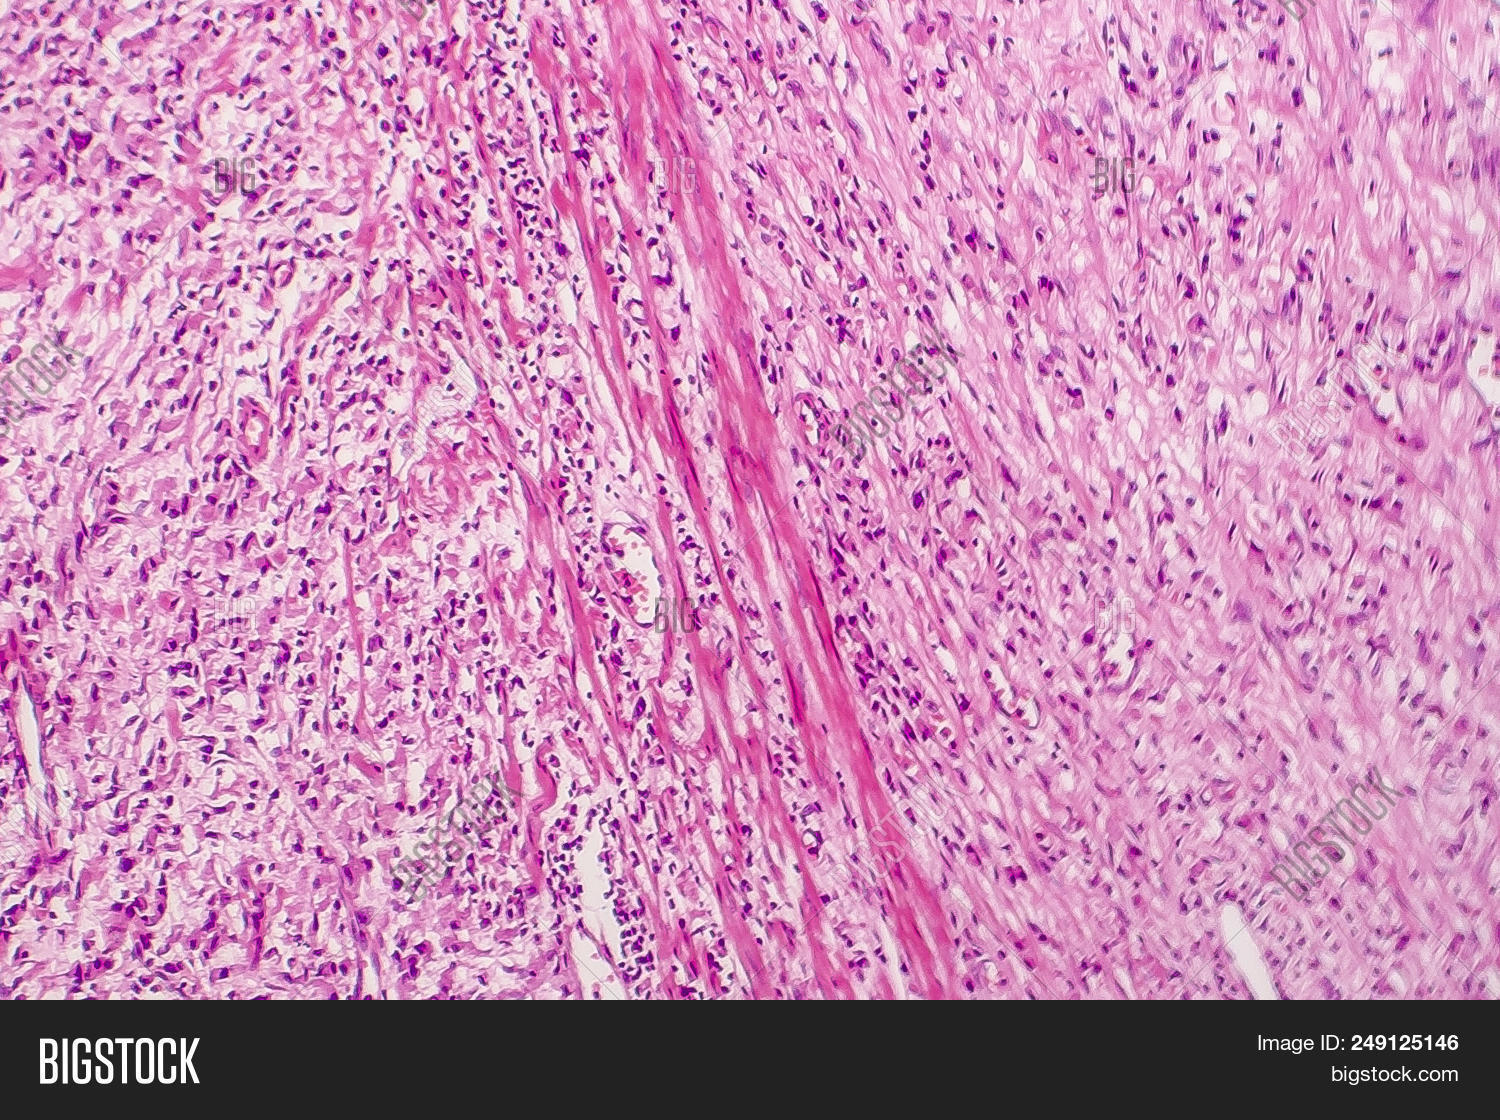

The name of the cell comes from its appearance; signet ring cells resemble signet rings. They contain a large amount of mucin, which pushes the nucleus to the cell periphery. The pool of mucin in a signet ring cell mimics the appearance of a finger hole and the nucleus mimics the appearance of the face of the ring in profile.